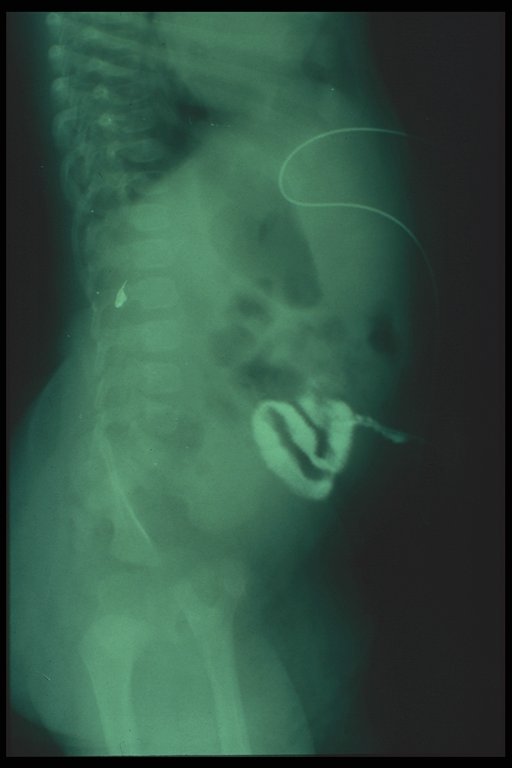

Fistulogram in a child with umbilical hernia and fistula demonstrates the connection to the intestine

Fistulogram demonstrated the tract connected between the umbilicus and the intestine

At operation, a patent vitelline duct is demonstrated connected between the umbilicus and Meckel's diverticulum